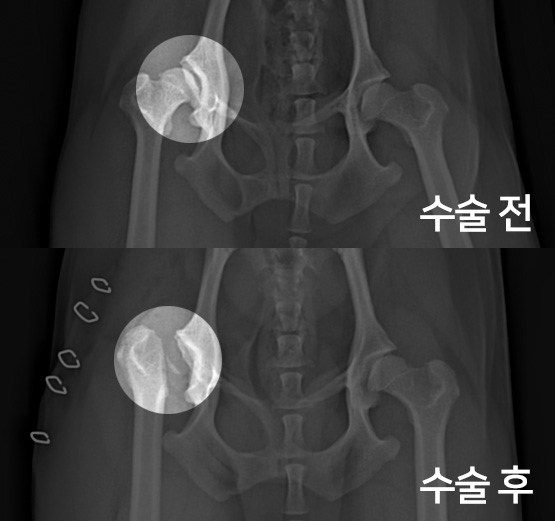

고관절 수술 사례 - #276 올리

올리는 고관절 수술 상담을 위해 내원하였습니다.

촉진 및 방사선 촬영 결과

대퇴골두 절골술(FHNO)이 필요하다고 판단되었습니다.

문제의 원인이 되는 대퇴골두를 깔끔하게 절단해 주었습니다.

수술 전과 수술 후 촬영한 고관절 방사선 사진입니다.

대퇴골두가 깔끔하게 절단된 것이 확인됩니다.

이제 재활 운동을 통해 체중을 지지할 근육을 키워주게 됩니다.